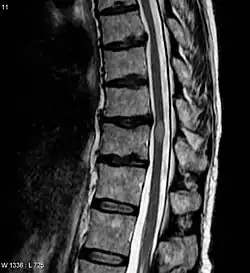

The most common initial manifestation of the disease is inflammation of the spinal cord (myelitis).[4] Myelitis causes spinal cord dysfunction, which can result in muscle weakness, paralysis in the limbs, lost or reduced sensation, spasms, loss of bladder and bowel control, or erectile dysfunction.[1][4][2][7][8][9] The myelitis can be transverse, affecting an entire cross-section of the spinal cord, and showing bilateral symptoms.

In NMOSD, areas of brain tissue that appear normal in conventional magnetic resonance imaging (MRI) can show damage in diffusion tensor imaging (DTI), although less so compared to multiple sclerosis (MS).[25]

Most research into the pathology of NMO has focused on the spinal cord. The damage can range from inflammatory demyelination to necrotic damage of the white and grey matters. The inflammatory lesions in NMO have been classified as type II lesions (complement-mediated demyelination), but they differ from MS pattern II lesions in their prominent perivascular distribution. Therefore, the pattern of inflammation is often quite distinct from that seen in MS.[18][26]

| Acute myelitis | intramedullary lesion > 3 contiguous segments, or spinal atrophy ≥ 3 contiguous segments |